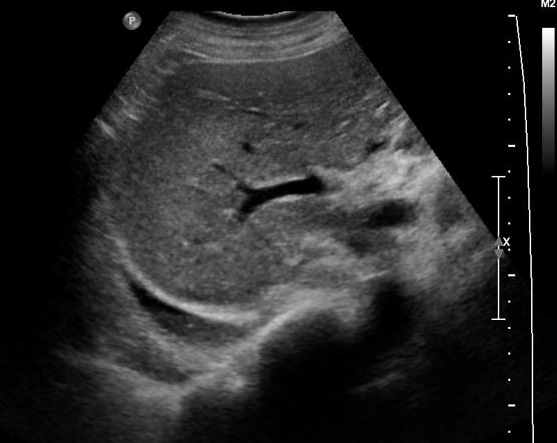

Aspect echographique d'une pleuresie du

sinus costo -diapragmatique postero-lateral droit .

La sinus costo-lateral droit remplir par pleuresie

aechogene |

Image echographique d'une

epanchement liquidien ( pleuresie ) du sinus

costo-diapragmatique droit en aspect de forme de

croissant aechogene de la region posterieure lateral

droit . Image echographique percutane en coupe

lateral droit . Echographie percutane

est la technique souvent utilise pour explorer

bien dans les cas epanchement à petite volume de

faible abondance . |